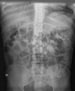

-

Abdominal radiographs confirm acute colonic pseudo-obstruction after hip surgery. Note extensive, diffuse colonic dilation with no evidence of transition point.